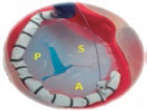

1. Mid-esophageal 4-chamber view at 0º. The septal leaflet (adjacent to the aorta) and the anterior leaflet (adjacent to the RV free wall) can be seen when the transducer is in anteflexion position (figure 1). The posterior leaflet can be seen when it is in the retroflexion position.

Figure 1. A: mid-esophageal 4-chamber view showing the septal leaflet and the anterior leaflet. B: imaginary view in the 4-chamber view. C: deep transesophageal view. A, anterior; TEE, transesophageal echocardiogram; S, septal; CS, coronary sinus.

To optimize the images of the right heart structures, the transducer should be turned clockwise. The artifacts of the septum and aortic or mitral valves can block the view of the septal leaflet. Tricuspid annulus is measured in this view with open flap-like cusps at the end of the diastole.

3. Deep esophageal 4-chamber view at 0°. Since the right inferior border of the heart is close to the diaphragm, the deepest insertion of the TEE transducer reaches the distal esophagus, close to the gastroesophageal junction; it may be that this view will only show the right atrium and coronary sinus and no images of the left atrium (figure 1). This prevents left heart structure-related artifacts from happening like the acoustic shadowing that the mitral prosthetic material can cause on the septal leaflet. This is the optimal view to acquire 3D volumes.